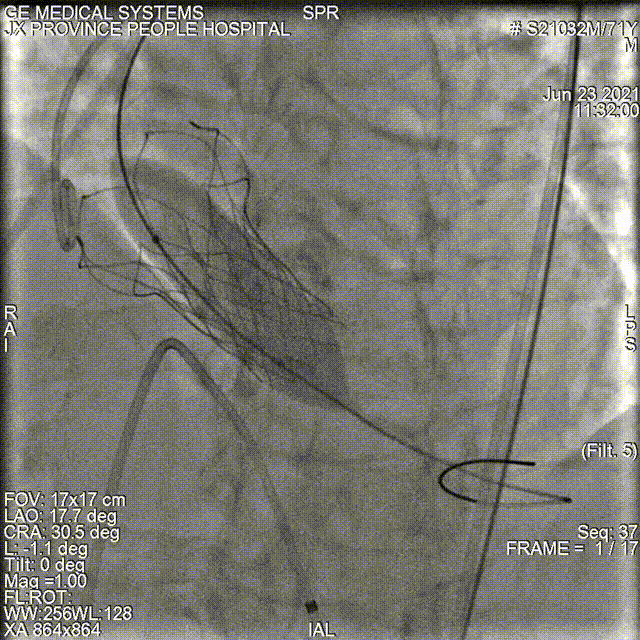

冠脉造影

敖广球囊18mm预扩张

同时进行冠脉风险评估:观察球囊扩张对冠脉的影响